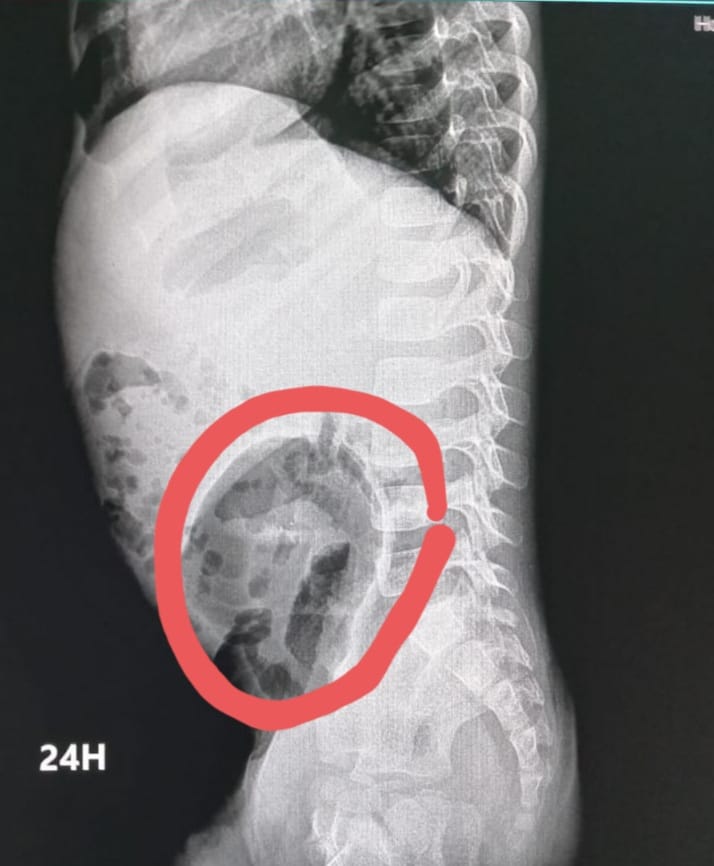

La doctora Idelsa Polanco encargada del departamento de gastroenterología del hospital pediátrico Hugo Mendoza explicó que el megacolon congénito también llamada Enfermedad de Hirschsprung es una ausencia de los ganglios nerviosos de la terminación del intestino, es decir el colon, cuya función es expulsar las heces fecales.

La especialista detalla que si no hay terminación, "la pupú se va acumulando en el colon y no hay quien la expulse hacia afuera y empieza a creer del tamaño de las heces fecales y se va quedando grande".

“La enfermedad se manifiesta en los primeros tres días del nacimiento el niño no evacúa, hace un taponamiento y hay que sacarle las heces fecales a través irrigaciones con algunos métodos", indicó la pediatra.

Otros síntomas en recién nacidos es el abdomen hinchado, vómitos frecuentes y estreñimiento o gases, que generan incomodidad en los bebés.

El doctor Elvyn Alcántara Encargado de la unidad colorrectal del hospital Robert Read dijo que se trata de un diagnóstico tardío porque durante 10 años asistido con supositorios de glicerina durante toda su vida para poder evacuar y precisamente ese es uno de los mayores signos de alarma.

"Mientras mayor tiempo, más el riesgo, hay niños que mueren de megacolon congénito no diagnosticado, si tu no puedes evacuar, tú te mueres, quizás por eso los padres desde los tiempos de antes ayudan a que el bebé pueda evacuar", narró el cirujano pediátrico.